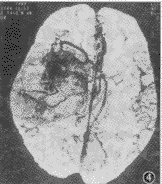

脑血管成像示:(1)55例CTA均可清楚显示1~4级脑血管结构、Willis环和大脑前、中、后动脉主干及其分支情况。(2)脑动静脉畸形12例,其中枕叶3例,颞叶5例,额叶3例,顶叶1例。可见异常增粗迂曲的血管,9例血管呈团状,5例可见增粗的引流血管,5例部分血管有钙化,均可清楚地观察到畸形血管的位置和范围(图1)。(3)动脉瘤2例,清楚地观察到瘤体大小、位置、形态,以及与血管的关系(图2,3)。(4)脑肿瘤19例,其中9例脑膜瘤可见肿瘤邻近血管被推移或包裹,4例可见肿瘤表面有异常血管(图4)。4例胶质瘤和4例转移瘤可见瘤体呈不均匀强化,或不强化,周围有不同程度水肿,肿瘤附近血管被推移(图5);位于第4脑室的室管膜瘤和位于中颅窝蝶骨翼旁的三叉神经瘤可见瘤体呈不同程度强化,室管膜瘤有血管推移。(5)大脑中动脉及分支栓塞3例,2例大脑中动脉主干变窄、变细,远侧方血管变细、变少(图6);1例大脑中动脉顶后分支变细,变窄,远侧方血管较少;(6)脑挫裂伤及脑脓肿可见局部血管有不同程度推移,脑积水以两侧大脑前、中动脉抬高较为明显。

图4 右颞叶脑膜瘤CTA,可见右颞叶有一巨大肿瘤,大脑中动脉向前推移,肿瘤表面有异常血管